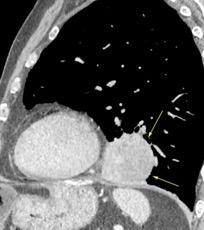

Signo de la Pleura separada “Split pleural sign”

Capas pleurales de grosor uniforme realzadas por el contraste

No específico de empiema. Indica “exudado”. 68% de pacientes con empiema pleural.

Capas pleurales de grosor uniforme

Realce grasa extrapleural (30%)

> Grasa Extrapleural. (60-80%)

Kraus GJ. Split pleural sign. Radiology 2007